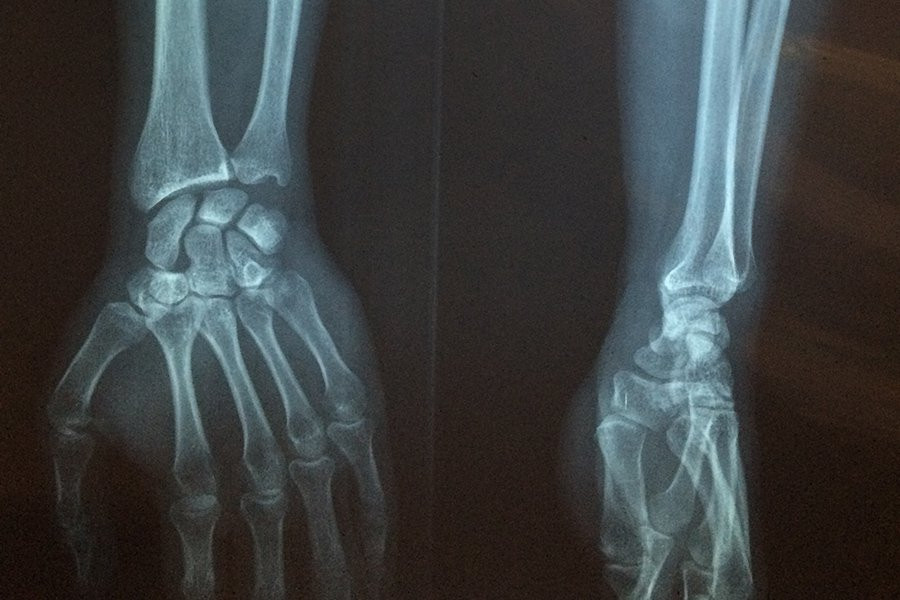

Во-первых, группа провела эксперименты по секвенированию на мышах с переломами костей и обнаружила, что TEs, особенно РНК LINE-1, были повышены в течение короткого периода времени после перелома.

Затем исследователи изучили TEs в костных клетках (остеобластах), взятых у женщин в постменопаузе с остеопорозом и у здоровой контрольной группы. TEs, в частности LINE, были сильно повышены в здоровых бедренных костях с высокой плотностью костей, в то время как у тех, у кого плотность костей ниже и остеопороз, наблюдалась низкая экспрессия LINE.